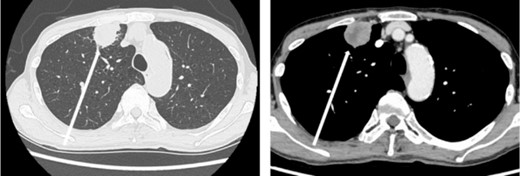

The patient was a 73-year-old man. He had a history of arteriosclerosis obliterans in the lower extremities, transient atrial fibrillation, and was consuming two antiplatelet agents. The patient had a fever within the range of 38°C. Blood tests showed an elevated white blood cell (WBC) count of 31.6 × 103/μl (neutrophil, 90.2%), CRP of 9.67 mg/dl, and APTT of 125.4 s. Chest radiography revealed an abnormal shadow in the upper lobe of the right lung (Fig. 1). Contrast-enhanced chest CT revealed an irregularly shaped mass, 43 × 33 × 28 mm in size, in the upper lobe of the right lung (Fig. 2). 18F-fluorodeoxyglucose-positron emission tomography showed abnormal accumulation with a maximum standardized uptake value of 28.4 in a pointed lesion in the upper lobe of the right lung (Fig. 3). A bronchoscopic biopsy was performed, and the patient was diagnosed with non-small cell carcinoma.

Chest computed tomography (CT) findings. An irregular mass 43 × 33 × 28 mm in size was found in the upper lobe of the right lung, which was suspected to be primary lung cancer.